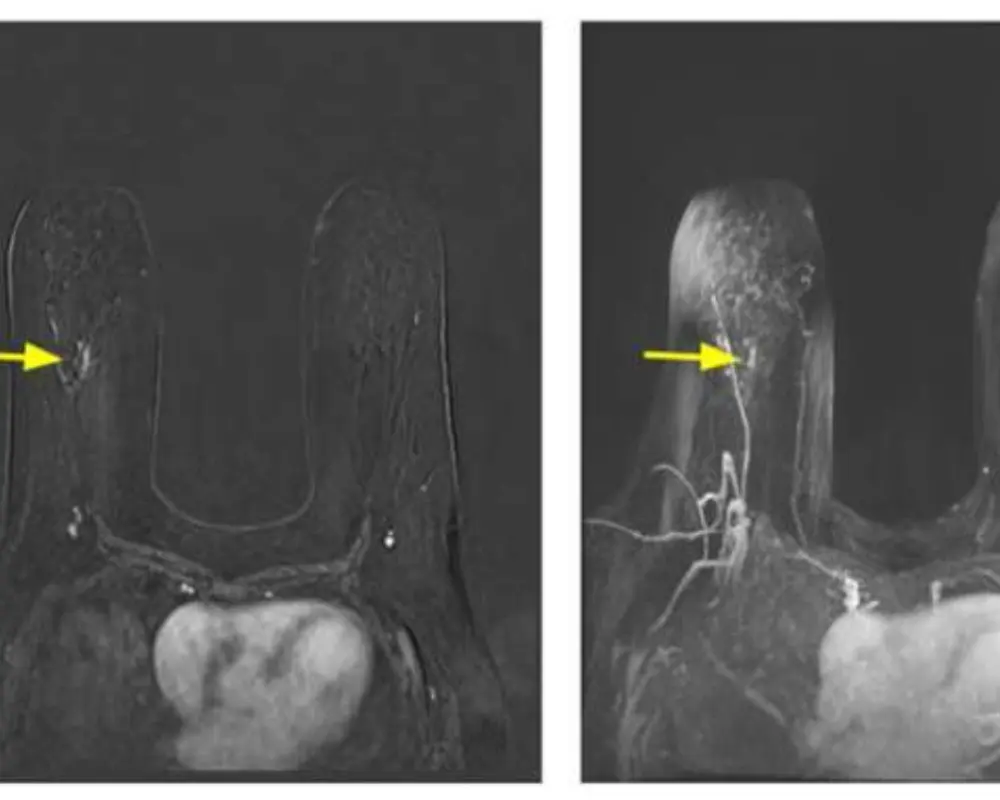

High Risk Screening MRI

Breast MRI is recommended for high risk patients with family history or genetic factors. It supports early screening by detecting abnormalities before symptoms develop and helps guide proactive monitoring and care decisions.

Breast MRI with Contrast

Breast MRI with contrast enhances image clarity by highlighting blood flow and abnormal areas. It helps improve detection of suspicious tissue and supports more accurate diagnosis during detailed breast MRI examinations.

Enhanced Imaging with Contrast

Breast MRI with contrast improves image clarity by highlighting blood flow and abnormal areas. It supports more accurate detection and helps provide deeper insight during a detailed breast MRI scan.